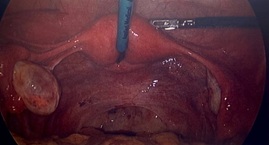

Diagnostics Previous pelvic ultrasound from 10th December 2020 had shown no abnormalities (Figure 1).

Figure 1: Ultrasound of the Pelvis from December 2020.